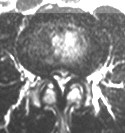

Ursache für die Spinalkanalstenose ist die verschleißbedingte Verschmälerung der Bandscheiben, die zu einer dauerhaften Fehlbeanspruchung und schließlich zur Arthrose der kleinen Wirbelgelenke führt. Die daraus resultierende Verdickung dieser Gelenke und der anliegenden Bänder führt zu einer Einengung des Wirbelkanals und der Nervenaustrittskanäle der Wirbelsäule. Dadurch kommt es zu einer dauerhaften mechanischen Reizung der Nerven. Gleichzeitig werden infolge des Verschleißprozesses chemische Reizstoffe frei, die den chronisch-entzündlichen Prozess im Wirbelkanal verstärken. Die Diagnose wird heutzutage mittels Kernspintomographie gestellt.